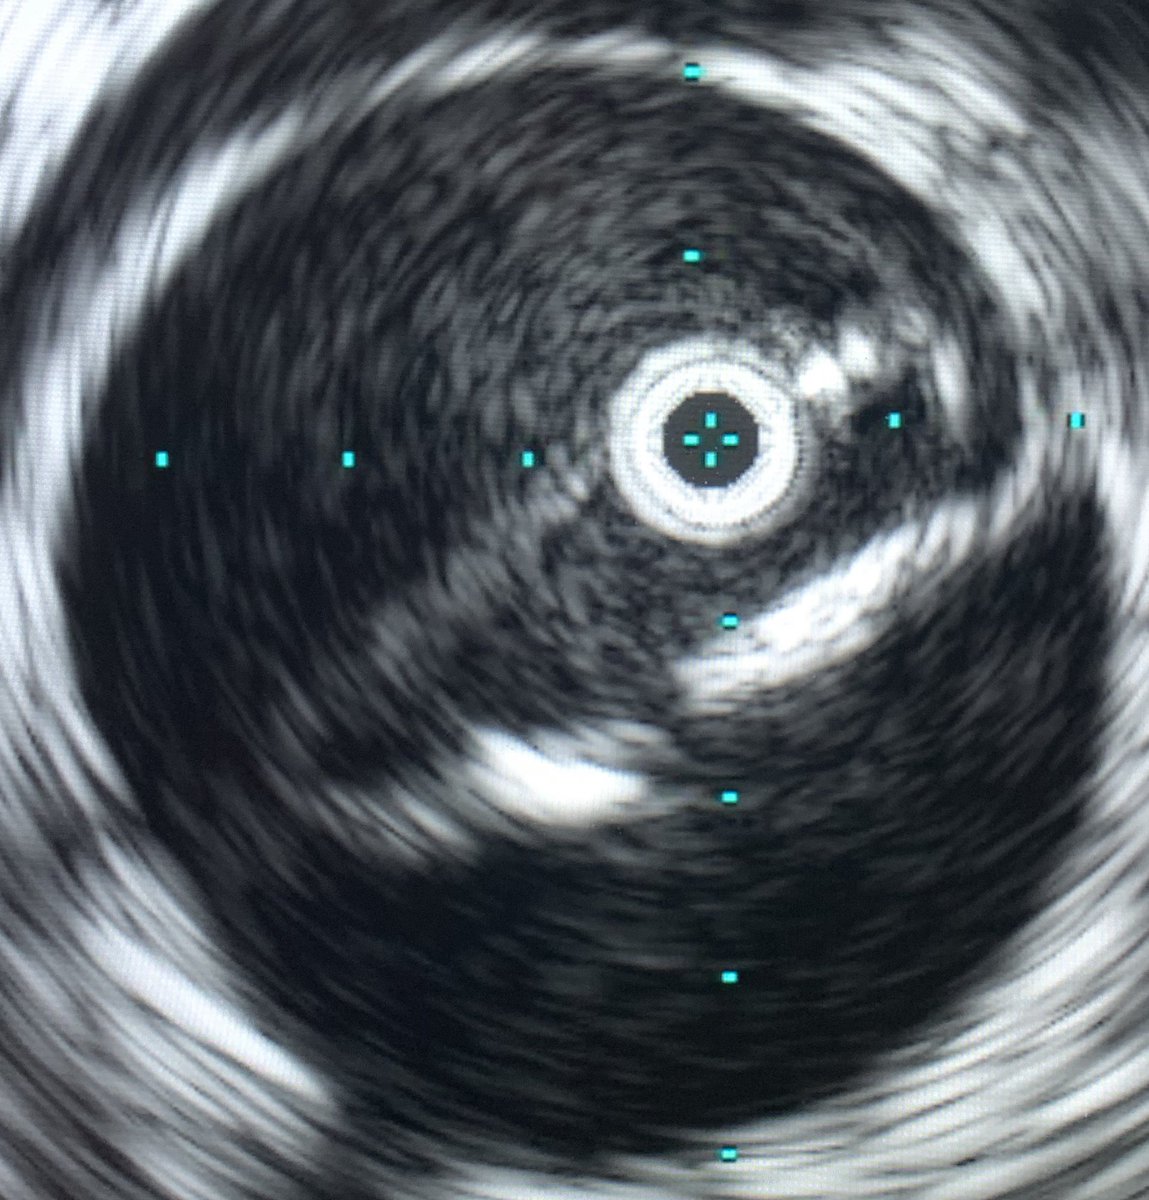

TBAD with rapid growth. Treated on D25 post event. Circumferential delamination in the perivisceral segment. Treated with #PETTICOAT @CookMedical @CAIRweb @anastasiah04